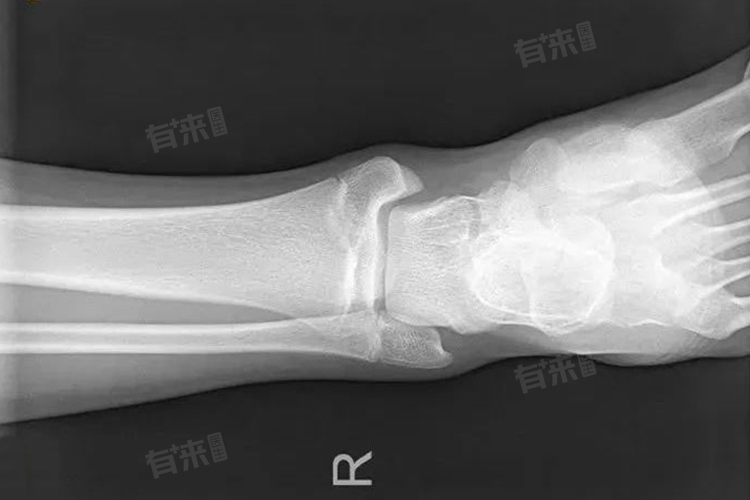

骨头闭合通常指骨骺闭合,标志着骨骼生长发育的结束,长骨两端的软骨板钙化形成坚硬骨组织,限制身高的自然增长空间,尽管遗传、营养、运动等因素可能对身高有微小影响。

- 骨骺闭合意味着长骨如大腿骨、小腿骨等两端的软骨板已经钙化,形成坚硬的骨组织,使得骨骼无法再通过软骨板的增殖来延长,因此从生理学的角度来看,骨头闭合后,身高的增长空间变得非常有限。